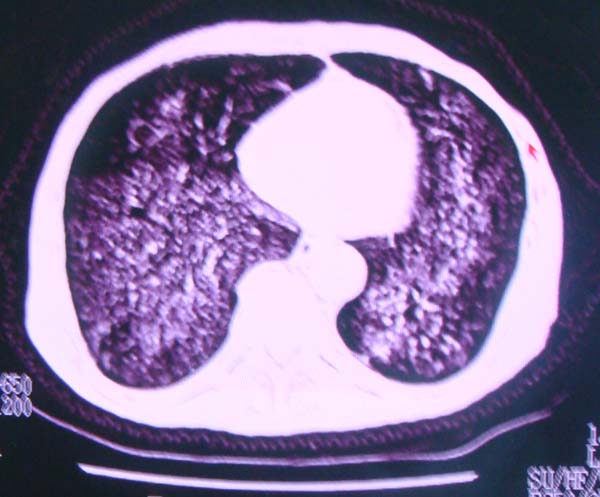

以下是引用zhangzhongshou在2008-2-15 22:25:00的发言:[br]片子照得不清,基本考虑1、细支气管肺泡癌2、亚急性血行播散型肺结核。请结合临床。片子细节显示不清,无法提供进一步意见。

以下是引用杀毒软件在2008-2-15 22:34:00的发言:[br]小叶中心性肺气肿。两肺弥漫性病变,肺泡微石病,过敏性肺炎,尘肺2期,特发性肺纤维化都有可能。[br]不象肺泡癌。